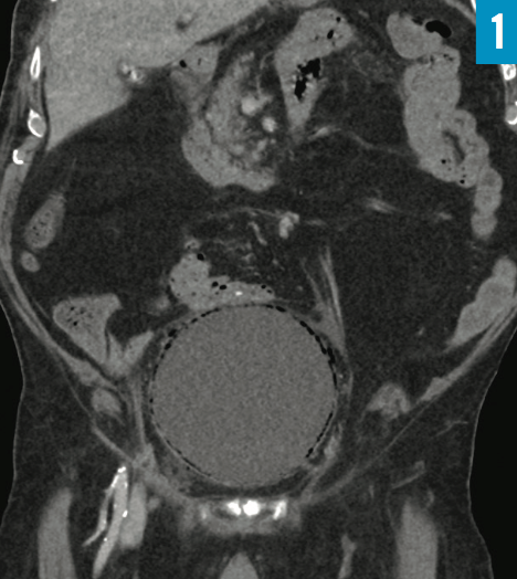

A 90-year-old man presented to the emergency department with 1-day history of tachypnea, dyspnea, and lower abdominal pain. His multiple comorbidities included coronary artery disease, obstructive sleep apnea, hypertension, hyperlipidemia, gout, transient ischemic attack, and benign prostatic hyperplasia with placement of a long-term indwelling urinary catheter for years.

His vital signs included a blood pressure of 156/79 mm Hg, a heart rate of 92 beats/min, a respiratory rate of 36 breaths/min, a temperature of 36.0°C, and oxygen saturation of 96% on room air. Abdominal examination revealed suprapubic tenderness without rebound tenderness or guarding. Urinalysis results were suggestive of urinary tract infection. Computed tomography scans of the abdomen/pelvis were obtained (Figures 1 and 2).